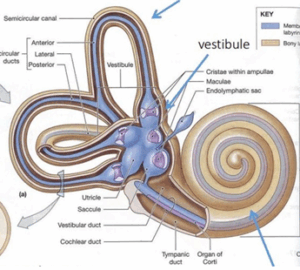

頸椎、側頭骨、顎関節および上顎骨の変形と緊張を含む頭蓋頸椎不安定性は、内耳のリンパ排出を停滞させ、内リンパ水腫を引き起こす構造的原因として、繰り返されるメニエール病の隠れた原因となる可能性があります。